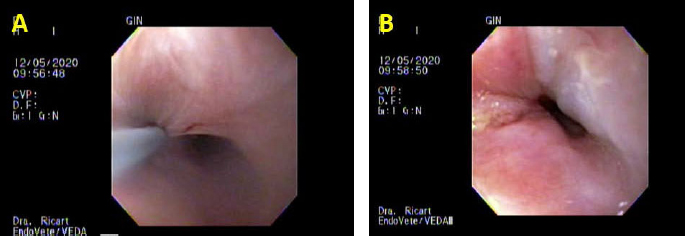

Fig. 3. Third day of endoluminal dilatation and second triamcinolone injection. (A) First quadrant injection in the submucosa with a per-endoscopic needle, 0.3 ml of triamcinolone acetate 40 mg/ml. (B) Evaluation of the endoluminal procedure after the four-quadrant injection. DiscussionThis case report describes successful therapy of recurrent esophageal strictures by combined endoscopic balloon dilatations in a cat local submucosal triamcinolone acetate injections that failed to respond to three balloon dilatations alone. In this clinical case, balloon dilatation was the therapeutic option, thus the stricture was annular; in other cases presenting long strictures, Savary–Gilliard dilatation is the better therapeutical option, and they need more dilatation sessions (Novais et al., 2008). Intralesional steroid injections have been suggested to inhibit the inflammatory response, thereby the stricture formation (Siersema, 2019). There were no differences in response outcomes between injections ranging from 0.5 to 2.8 ml of triamcinolone acetate or acetonide 10 or 40 mg/ml in human medicine Poincloux et al., 2017 In veterinary medicine, as to the authors’ knowledge, there are no specific guidelines with regard to the injection dose. The dose in this clinical case (triamcinolone acetate 40 mg/ml 0.3 ml in each quadrant) was chosen empirically. This is the range used in human medicine. The cat did not develop any complications associated with the high dose of corticosteroids. Double-blinded prospective studies are necessary to evaluate the range of dose for cats and dogs and guidelines for its use. Systemic corticosteroids have questionable efficacy in the prevention of esophageal strictures in human beings and dogs (Poincloux et al., 2017). It may be argued that a successful outcome in this clinical case might have been achieved with a fourth or fifth balloon dilatation procedure alone without the corticosteroid injections. There are reports of successful outcomes achieved in 88% of canines and felines with endoscopic balloon dilatation with a range of one to five procedures (Fraune et al., 2009). In another retrospective study of canine and feline animals suffering from esophageal strictures, despite one to four balloon dilation procedures (mean=3), stenosis recurred and subsequent esophageal stenting was chosen as an alternative therapeutic procedure. This article mentions that this procedure was performed in five dogs and in three cats; in these seven animals the stenting was successful; however, three had mild and three of them had severe discomfort evaluated as poor tolerance, ptyalism, persistence of occasional regurgitations, or needed progressive stent removal and replacement. In the three cats, trichobezoar caught was observed (Da Riz et al., 2021). It should be taken into account that the European Society of Gastrointestinal Endoscopy does not recommend permanent stent placement in humans for refractory benign stricture; stents should usually be removed at a maximum of 3 months following insertion (Spaander et al., 2021). The frequency at which the procedures were performed was not possible to control; unfortunately, the indication of repeating the procedure every 4–7 days was not a possibility in this clinical case. The third dilatation was delayed for 30 days because of owners’ personal reasons. As the American Heart Association and the American Society of Gastrointestinal Endoscopy do not recommend routine antibiotic coverage prophylaxis in human medicine, even if bacteremia is the most common complication that occurs in 2%–23% of the cases (Poincloux et al., 2017), it was decided not to give amoxicillin/clavulanic acid or other broad-spectrum antibiotics as other clinical reports in dogs or cats had empirically decided before (Corgozinho et al., 2009; Fraune et al., 2009; Poincloux et al., 2017). The cat showed no clinical signs of bacteremia as a consequence of the dilatation procedures in either session. The use of routine antibiotic coverage prophylaxis in dogs and cats should be reconsidered because of its concern for increased antimicrobial resistance and long-term changes in microbiota composition (Ziese and Suchodolski, 2021). ConclusionThe alternative to triamcinolone injection after balloon dilatation presented in this clinical report was successful and it could be a therapeutic option for recurrent esophageal strictures in cats as it is in human medicine. The clinical signs of strictures depend on the degree of obstruction; most of the time there is a gradual progression as the stricture continues to contract, with more pronounced regurgitation and dysphagia; clinicians should take into account this differential diagnosis. AcknowledgmentThe authors would like to acknowledge the authorization from the family of the cat for the publication of the case report. Authors’ contributionsMCR: case evaluation, endoscopic management, manuscript drafting, and approval of the final manuscript; SMR: case evaluation, anesthesia administration and monitoring, critical revisions, and approval of the final manuscript; GD: endoscopic guidance, critical revisions, and approval of the final manuscript. Conflicts of interestAll authors declare that there are no conflicts of interest. ReferencesCorgozinho, K.B., Neves, A., Belchior, C., Toledo, F., Moreira de Souza, H.J. and da Hora, A.S. 2009. Uso de triancinolona local em uma gata com estenose esofágica. Acta Sci. Vet. 34, 175–178. Da Riz, F., Béguin, J., Manassero, M., Faucher, M. and Freiche, V. 2021. Outcome of dogs and cats with benign oesophageal strictures after balloon dilatation or stenting: 27 cases (2002–2019). J. Small Anim. Pract. 62(10), 886–894. Fraune, C., Gaschen, F. and Ryan, K. 2009. Intralesional corticosteroid injection in addition to endoscopic balloon dilation in a dog with benign oesophageal strictures. J. Small Anim. Pract. 50, 550–553. German, A.J., Cannon, M.J., Dye, C., Booth, M.J., Pearson, G.R., Reay, C.A. and Gruffydd-Jones, T.J. 2005. Oesophageal strictures in cats associated with doxycycline therapy. J. Feline Med. Surg. 7(1), 33–41. Kook, P.H. 2021. Esophagitis in cats and dogs. Vet. Clin. North Am. Small Anim. Pract. 51, 1–15. Novais, P., Lemme, E., Equi, C., Medeiros, C., Lopes, C. and Vargas, C. 2008. Estenoses benignas de esôfago: abordagem endoscópica com velas de Savary-Gilliard [Benign strictures of the esophagus: endoscopic approach with Savary-Gilliard bougies]. Arq Gastroenterol. 45(4), 290–4. Poincloux, L., Rouquette, O. and Abergel, A. 2017. Endoscopic treatment of benign esophageal strictures: a literature review. Exp. Rev. Gastroenterol. Hepatol. 11(1), 53–64. Siersema, P.D. 2019. How to approach a patient with refractory or recurrent benign esophageal stricture. Gastroenterology 156, 7–10. Spaander, M.C.V., van der Bogt, R.D., Baron, T.H., Albers, D., Blero, D., de Ceglie, A., Conio, M., Czakó, L., Everett, S., Garcia-Pagán, J.C., Ginès, A., Jovani, M., Repici, A., Rodrigues-Pinto, E., Siersema, P.D., Fuccio, L. and van Hooft, J.E. 2021. Esophageal stenting for benign and malignant disease: European Society of Gastrointestinal Endoscopy (ESGE) Guideline—update 2021. Endoscopy 53(7), 751–762. Szapáry, L., Tinusz, B., Farkas, N., Márta, K., Szakó, L., Meczker, A., Hágendorn, R., Bajor, J., Vincze, Á., Gyöngyi, Z., Mikó, A., Csupor, D., Hegyi, P. and Erőss, B. 2018. Intralesional steroid is beneficial in benign refractory esophageal strictures: a meta-analysis. World J. Gastroenterol. 24(21), 2311–2319. Tan, D., Weisse, C., Berent, A. and Lamb, K.E. 2017. Prospective evaluation of an indwelling esophageal balloon dilatation feeding tube for treatment of benign esophageal strictures in dogs and cats. J. Vet. Intern. Med. 32, 693–700. Ziese, A.N. and Suchodolski, J.S. 2021. Impact of changes in gastrointestinal microbiota in canine and feline digestive diseases. Vet. Clin. North Am. Small Anim. Pract. 51, 155–169. | ||